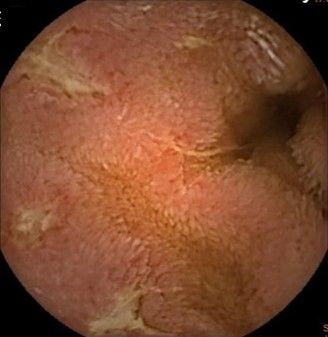

▲膠囊內視鏡下小腸中段的縱向潰瘍。(圖/馬偕醫院提供)

他說,該名患者經轉診到馬偕醫院後,經由膠囊內視鏡檢查,才發現小腸自空腸至迴腸處,有多處跳躍式病灶與縱向潰瘍,並綜合影像檢查、病理檢查等資訊排除其他可能性,結合患者臨床症狀表現診斷為克隆氏症,經過類固醇與免疫調節藥物治療後,目前患者情況已趨於穩定。

章振旺表示,小腸疾病較難以利用傳統腸鏡檢查一窺全貌,臨床上會仰賴膠囊內視鏡補足此一盲點,對克隆氏症早期發現與評估病灶嚴重程度有極大幫助。